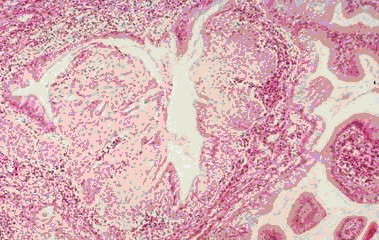

举例来说,慢性宫颈炎(宫颈糜烂)与宫颈癌在妇科阴道镜检查时观察到的表现可以相似。行宫颈刮片的细胞检查时看到的也可以相似(图1、2)。最后采取组织行病理切片检查,也是有相似之处,不是容易做出100%鉴别的(图3、4)。这样看来,如果仅一次检查(或一家医院检查),就肯定是癌,而行手术切除,是不慎重的,错误率是高的。最好是如果要手术切除,应到第二家医院或第二个医生核实后进行下一步治疗。

图3 宫颈炎看到的切片